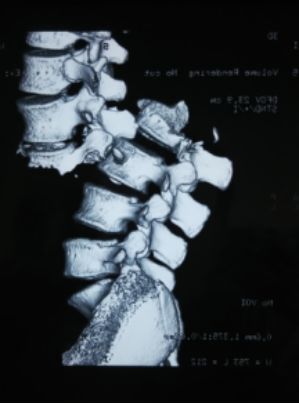

2、CT:可显示椎体的骨折情况,可显示有无碎骨片突出于椎管内,计算椎管前后径损失了多少,不能显示脊髓受损情况。(平扫、薄扫、三维、表面重建等)

(2)爆裂骨折

椎体压缩骨折的一种特殊形式,椎体呈粉碎骨折,骨折块向四周移位,向后移位可压迫脊髓、神经,椎体前后径和横径均增加,两侧椎弓根距离加宽,椎体高度减小。